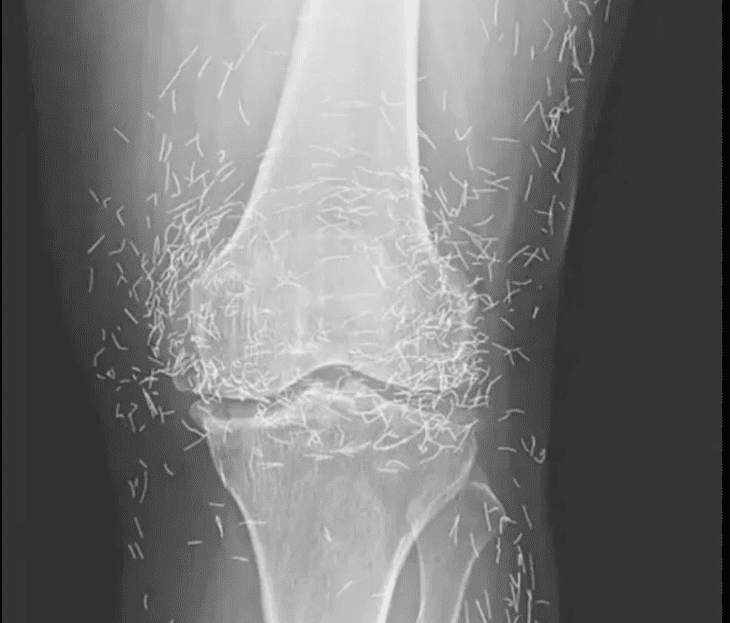

Une radiographie révèle des centaines d’aiguilles en or dans les genoux d’une femme

En examinant une radiographie des genoux d’une femme âgée souffrant de fortes douleurs articulaires, les médecins ont découvert une mine d’or : des centaines de minuscules aiguilles d’acupuncture en or, restées dans ses tissus.

Lors du traitement d’acupuncture de cette femme, les aiguilles, vraisemblablement en or, ont été intentionnellement laissées dans ses tissus pour une stimulation continue, indique le rapport.